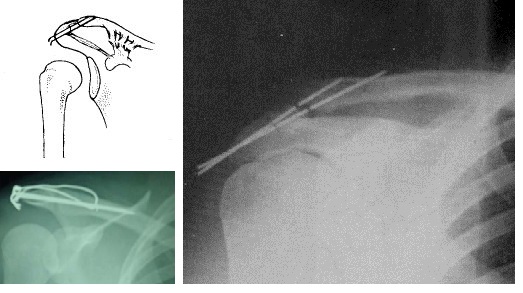

对于肩胛骨与锁骨之间,过去是用克氏针固定的,包括交叉克氏针和克氏针张力带,但是因为肩锁关节是半活动关节,常会因反复作用的剪切力造成克氏针断裂,而且断端有时特别难取出。

所以人们发明了锁骨钩钢板,现在最主流的固定方式,它既避开了韧带区,又实现了刚性限制下的弹性固定,右图是固定后的X片。